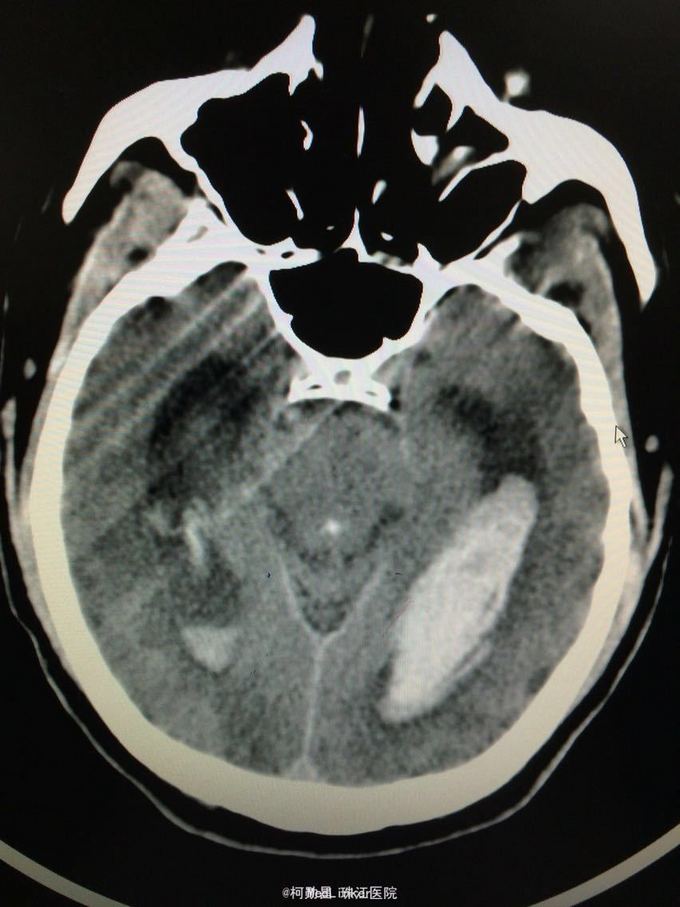

主诉:突发意识障碍4小时 病史:患者57岁男性,入院前一天晚上突发意识不清,伴呕吐胃内容物多次,无肢体抽搐等,随即由家人呼叫120送至我院,急诊行头颅CT提示左侧基底节区出血破入脑室。既往高血压病史10多年

查体:神志不清,双侧瞳孔散大,对光反射消失,四肢肌张力正常,肌力无法检查 辅助检查:头颅CT提示左侧基底节区出血破入脑室

诊断:左侧基底节区出血并破入脑室 处理:急诊行侧脑室钻孔外引流术,术后并予积极抢救,最终抢救无效死亡